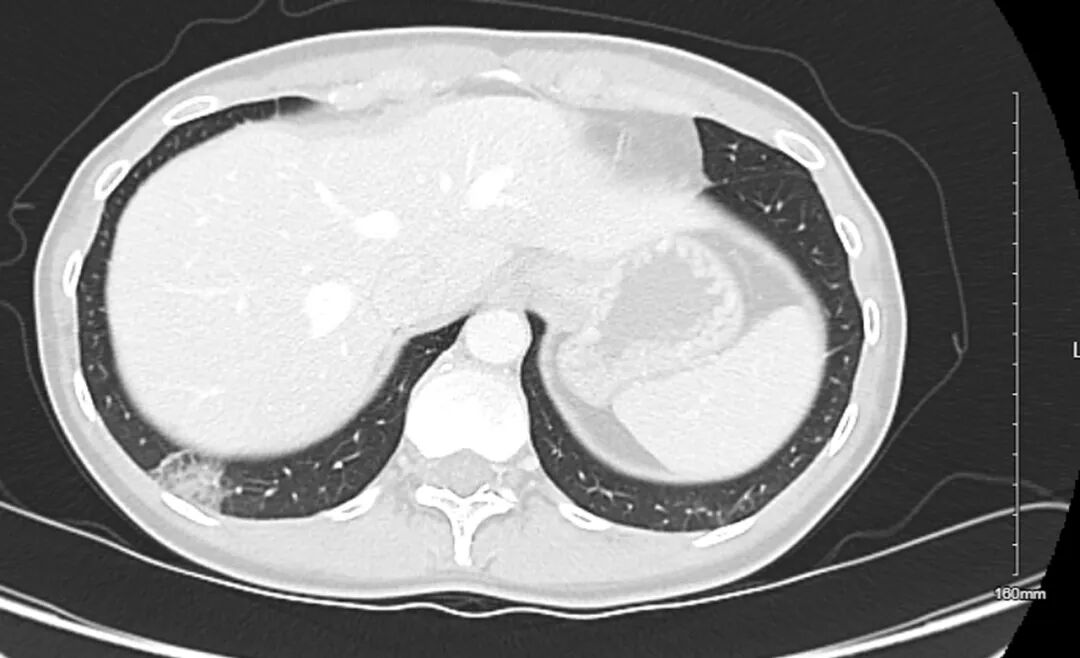

,内含致密磨玻璃及部分实性衰减成分,所见其余肺野无异常发现(图1)。泌尿科医生在患者初次就诊后6周后安排的随访CT成像中,2.4厘米的亚实性肺结节持续存在,其大小及实性成分(测量至少8毫米)均未见明显变化(图2)。患者被转诊至肺结节门诊。

图2. 初次检查(图1)后6周复查的腹部盆腔增强CT扫描图像。结果显示,2.4厘米的亚实性肺结节持续存在,其大小及实性成分均未见明显变化。